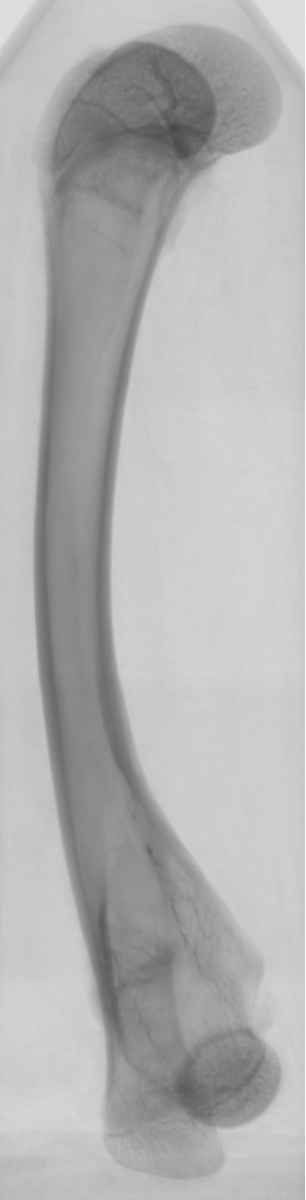

骨骼组织的三维重建

显微 CT 可以以非破坏性的方式对骨骼组织进行三维成像,包括骨小梁的连通情况、骨密度分布等信息。这为人工骨骼的设计与制备提供了关键的参考,也可用于研究骨骼力学特性及其在仿生工程中的应用。